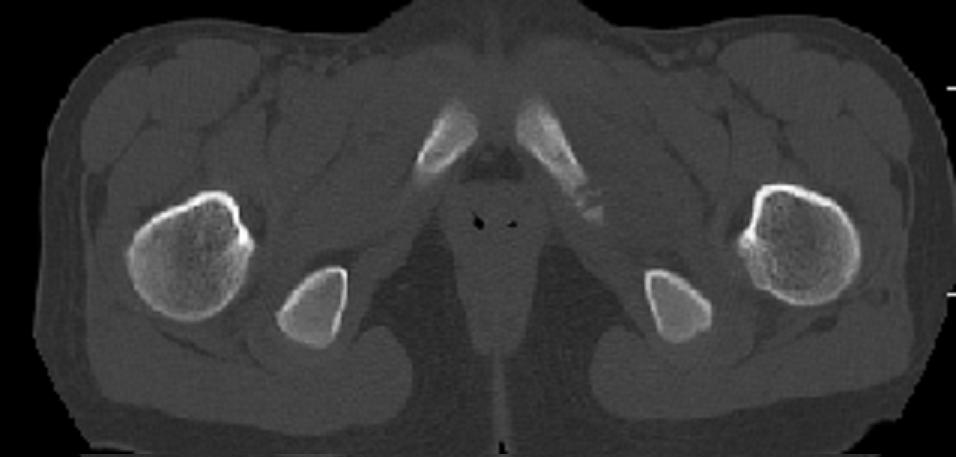

以下是引用zxd95在2008-7-2 10:06:00的发言:[br]左耻骨下支局部骨质破坏,内见小条状小骨片,周围肌间隙模糊,左闭孔内外肌肿胀。[br]儿童患者,首先考虑结核性,以骨质破坏为主(其内小条状小骨片解释为死骨)。[br]鉴别:[br]1、化脓性病变以增生为主;[br]2、肿瘤性病变:良性肿瘤不会有周围软组织的肿胀、模糊;恶性肿瘤病变骨皮质破坏、中断;[br]3、肿瘤样病变:一般也无周围软组织的改变。[br]建议查肺部及结核相关实验室检查。

以下是引用dyqct在2008-7-2 15:38:00的发言:[br]左坐骨与耻骨交界处膨胀性溶骨性病变,周围软组织略肿胀,边界不清。[br]发生在这个年龄组该部位最常见的一种发育变异,可以出现此种改变。另外感染不除外,建议定期复查。